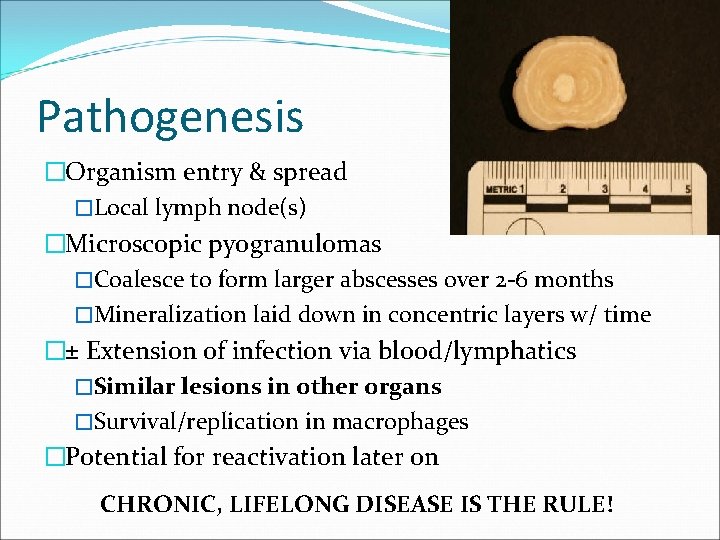

Pathogenesis �Organism entry & spread �Local lymph node(s) �Microscopic pyogranulomas �Coalesce to form larger abscesses over 2 -6 months �Mineralization laid down in concentric layers w/ time �± Extension of infection via blood/lymphatics �Similar lesions in other organs �Survival/replication in macrophages �Potential for reactivation later on CHRONIC, LIFELONG DISEASE IS THE RULE!